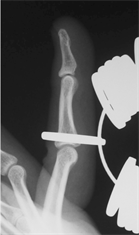

measurements. The minimum number of the ring gauge size that allowed the IP thumb joint and PIP finger joints, from the index finger to the little finger, to pass through was recorded. The positions that were actually measured by the ring gauges were the site at which weak resistance occurred (Figure 2(a)), the site at which maximum resistance occurred (Figure 2(b)) and the site at which resistance was attenuated (Figure 2(c)) when the finger was inserted into the ring. We measured the point at which there was maximum resistance, i.e. at Figure 2(b). RG was defined as the ring gauge number with the same diameter as the circumference of the IP thumb joint and PIP finger joints from the index finger to the little finger.

(a) (b) (c)

Figure 2. Measurement position for the ring gauge, (a) Distal end causing resistance; (b) Position at which maximum resistance occurs; (c) Position has passed the proximal part of the PIP.